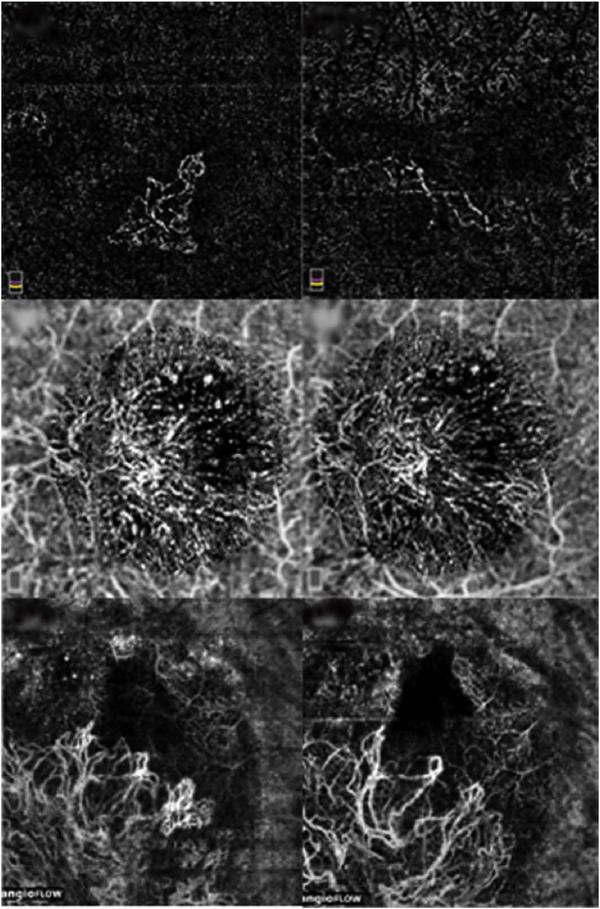

Optical coherence tomography (OCT) was one of the biggest advances in ophthalmic imaging. Building on that platform, OCT angiography (OCTA) provides depth resolved images of blood flow in the retina and choroid with levels of detail far exceeding that obtained with older forms of imaging. This new modality is challenging because of the need for new equipment and processing techniques, current limitations of imaging capability, and rapid advancements in both imaging and in our understanding of the imaging and applicable pathophysiology of the retina and choroid. These factors lead to a steep learning curve, even for those with a working understanding dye-based ocular angiography. All for a method of imaging that is a little more than 10 years old. This review begins with a historical account of the development of OCTA, and the methods used in OCTA, including signal processing, image generation, and display techniques. This forms the basis to understand what OCTA images show as well as how image artifacts arise. The anatomy and imaging of specific vascular layers of the eye are reviewed. The integration of OCTA in multimodal imaging in the evaluation of retinal vascular occlusive diseases, diabetic retinopathy, uveitis, inherited diseases, age-related macular degeneration, and disorders of the optic nerve is presented. OCTA is an exciting, disruptive technology. Its use is rapidly expanding in clinical practice as well as for research into the pathophysiology of diseases of the posterior pole.

光学相干断层扫描(OCT)是眼科成像领域的重大突破之一。在此基础上,OCT 血管造影术(OCTA)提供了视网膜和脉络膜血流的深度分辨图像,其细节水平远远超过了旧的成像方式。这种新的模式具有挑战性,因为需要新的设备和处理技术,目前成像能力的限制,以及成像和对视网膜和脉络膜成像及适用病理生理学的理解的快速发展。这些因素导致学习曲线陡峭,即使对于那些对基于染料的眼部血管造影术有一定了解的人来说也是如此。所有这些都是为了一种成像方法,它的历史还不到 10 年。这篇综述从 OCTA 的发展历史和 OCTA 中使用的方法开始,包括信号处理、图像生成和显示技术。这是理解 OCTA 图像显示内容以及图像伪影产生原因的基础。本文还回顾了眼部特定血管层的解剖结构和成像。介绍了 OCTA 在评估视网膜血管阻塞性疾病、糖尿病性视网膜病变、葡萄膜炎、遗传性疾病、年龄相关性黄斑变性和视神经疾病的多模态成像中的整合。OCTA 是一种令人兴奋的、颠覆性的技术。它在临床实践中的应用以及对后极部疾病病理生理学的研究中迅速扩展。